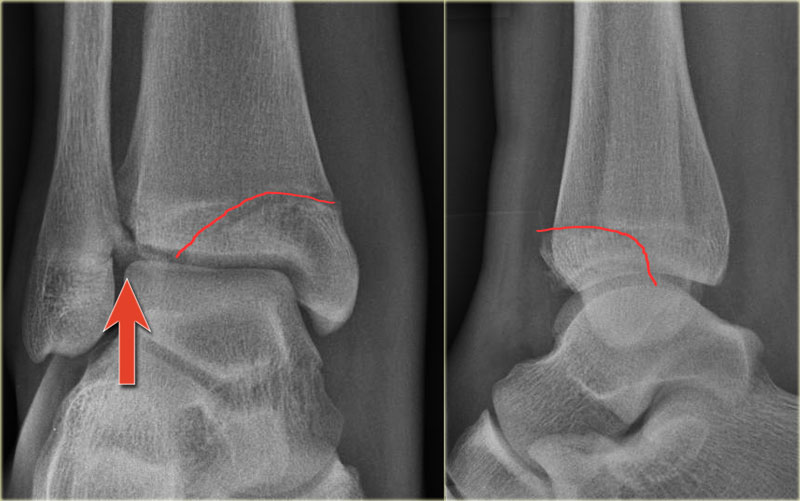

Hãy quan sát các hình ảnh và tiếp tục đọc phần bên dưới.

Thoạt nhìn, hình ảnh này có vẻ giống gãy xương Weber B với đường gãy chéo ở xương mác quan sát thấy trên tư thế chụp nghiêng (mũi tên đen).

Tuy nhiên, cần lưu ý rằng đường gãy này dừng lại ở mức sụn tiếp hợp.

Đây chính là đường gãy hành xương trên mặt phẳng trán.

Trên tư thế chụp thẳng (AP), có thể thấy một vùng thấu quang trong lòng đầu xương, tương ứng với đường gãy đầu xương trên mặt phẳng đứng dọc.

Cũng cần chú ý rằng sụn tiếp hợp phía trong đã đóng, trong khi phần ngoài vẫn còn mở (mũi tên xanh).

Chúng ta cần giả định rằng có hiện tượng tách sụn tiếp hợp (epiphysiolysis) ở phần ngoài này.

Đây là một ví dụ khác.

Mảnh gãy hành xương rất nhỏ, đây thường là trường hợp hay gặp (mũi tên đỏ).

Đường gãy qua đầu xương được chỉ thị bằng mũi tên xanh.